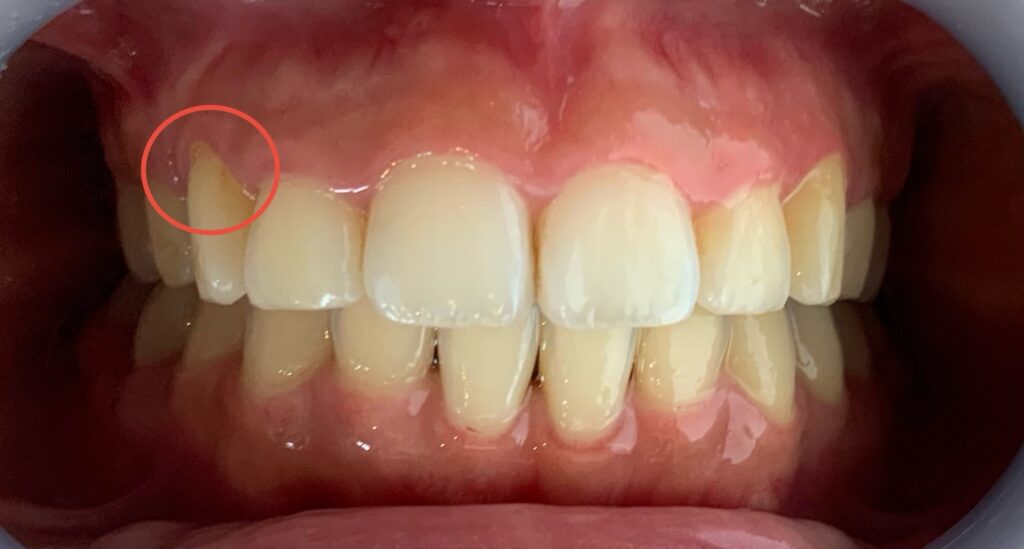

先日の犬歯に合わせて歯ぐきの形を整えた症例です。

赤丸で囲っている部分。

切除していないのに、術後の写真は出血しています。

なぜでしょうか。

答えは、歯肉炎です。

犬歯は歯冠長延長はしていないのですが、術後に消毒薬をつけた綿球でなぞった際に、その刺激で出血しました。